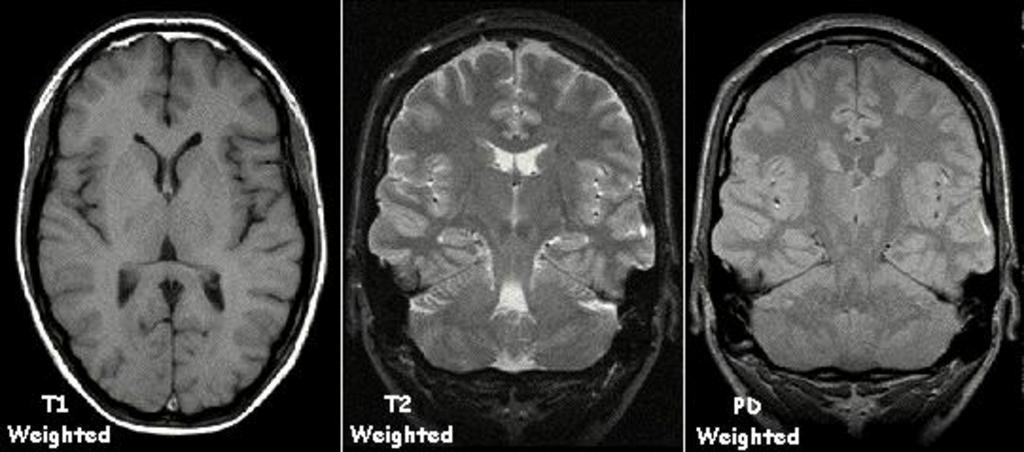

| Keywords: T1t2PD.jpg Examples of T1 weighted T2 weighted and PD weighted MRI scans Adapted with permission by Kieran Maher using Graphic Converter from http //homepage mac com/kieranmaher/ait/ Applied Imaging Technology by Heggie Liddell Maher 2000 2006-11-08 KieranMaher wikibooks en b English Wikibooks KieranMaher Original upload log page en wikibooks T1t2PD jpg 2006-11-08 10 04 KieranMaher 541×239× 30655 bytes <nowiki>Examples of T1 weighted T2 weighted and PD weighted MRI scans Adapted with permission by Kieran Maher using Graphic Converter from http //homepage mac com/kieranmaher/ait/ Applied Imaging Technology by Heggie Liddell Maher 2000 </nowiki> Magnetic resonance imaging of the brain | ||||